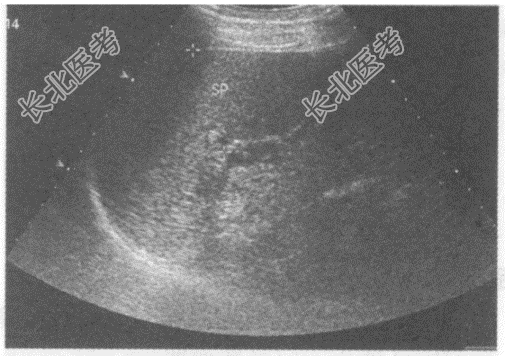

- 单项选择题临床资料:男性患者, 62岁,自述右上腹不适, 持续性隐痛;乙型肝炎病史20年, 胃镜发现食道静脉曲张。

超声综合描述:肝回声明显不均, 有结节感,三支肝静脉变细, 肝中裂增宽,门静脉内径1.4cm; 脾厚4.8cm,脾长径14.7cm。

超声提示: A、慢性酒精中毒性肝病门静脉增宽脾大

B、肝弥漫性肝癌门静脉增宽脾大

C、肝硬化门静脉增宽脾大

D、先天性肝纤维化门静脉增宽脾大

E、肝脓肿门静脉增宽脾大